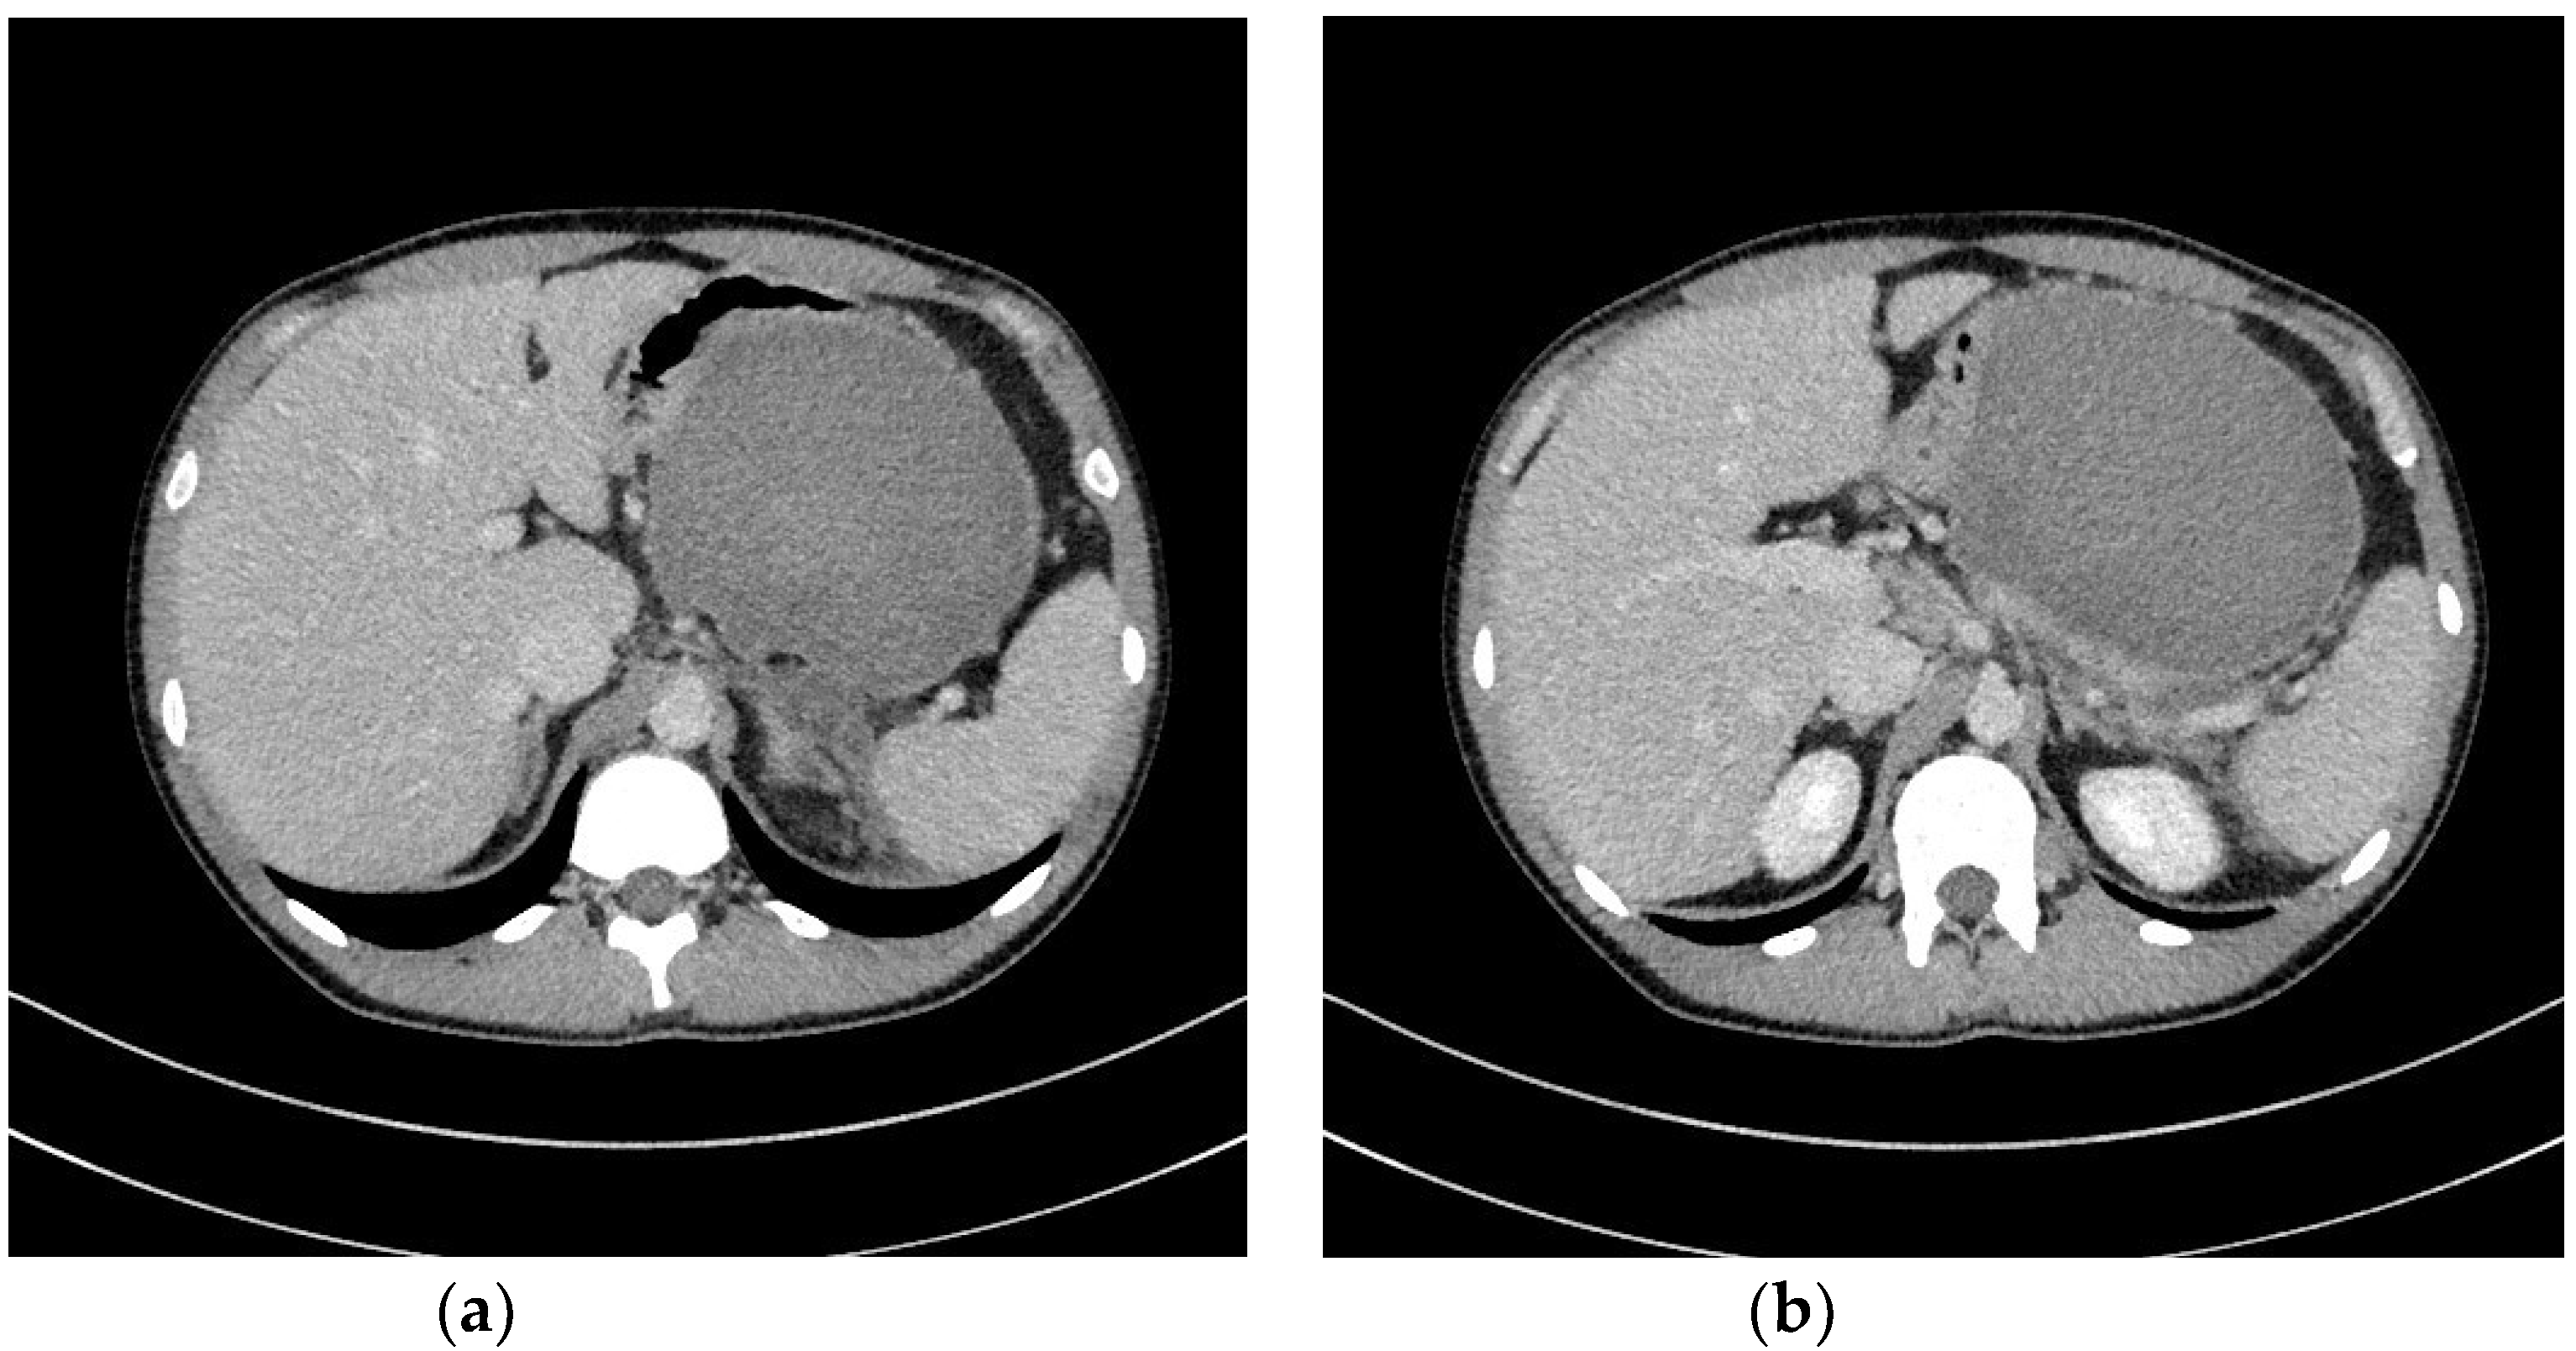

- Jagielski, M.; Smoczyński, M.; Jabłońska, A.; Marek, I.; Dubowik, M.; Adrych, K. The role of endoscopic ultrasonography in endoscopic debridement of walled-off pancreatic necrosis—A single center experience. Pancreatology 2015, 15, 503–507. [Google Scholar] [CrossRef]

- Smoczyński, M.; Marek, I.; Dubowik, M.; Rompa, G.; Kobiela, J.; Studniarek, M.; Pieńkowska, J.; Adrych, K. Endoscopic drainage/debridement of walled-off pancreatic necrosis—Single center experience of 112 cases. Pancreatology 2014, 14, 137–142. [Google Scholar] [CrossRef] [PubMed]

- Jagielski, M.; Smoczyński, M.; Studniarek, M.; Adrych, K. Endoscopic drainage combined with percutaneous drainage in treatment of walled-off pancreatic necrosis- a single center experience. Prz. Gastroenterol. 2018, 13, 137–142. [Google Scholar] [CrossRef] [PubMed]

- Jagielski, M.; Smoczyński, M.; Jabłońska, A.; Adrych, K. The development of endoscopic techniques for treatment of walled-off pancreatic necrosis (WOPN)—A single center experience. Gastroenterol. Res. Pr. 2018, 24, 36–41. [Google Scholar] [CrossRef] [PubMed]